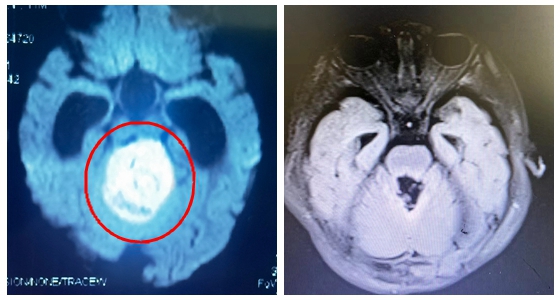

湘雅常德医院神经外科主任刘景平第一时间了解了患儿的发病过程及影像检查:患儿为小脑--四脑室占位,大小约为46mm*40mm*35mm。刘景平初步考虑患儿可能是:髓母细胞瘤,而这一病变导致了脑积水和间质性脑水肿的发生。

手术前后对比图

问题这么棘手,父母心情又陷入了无助和悲伤中。看着焦急又无助的父母,刘景平团队选择了扛下这个重担。神经外科团队组织麻醉手术部、输血科等,针对患儿的复杂病情制定了详细的手术方案,充分评估术中可能面临的风险及手术预案。在做好一切准备后,为西西安排了累及脑干的四脑室肿瘤切除术,术中仔细分离肿瘤与周围组织,在保护脑干功能前提下全切除病变,成功完成了手术。手术过程顺利,出血控制良好,无明显神经损伤加重表现。术后患儿恢复良好。